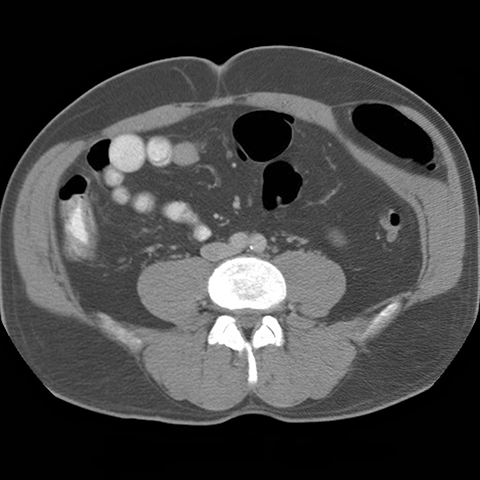

59 year-old male presents with an abdominal mass and pain. [4 of 5]